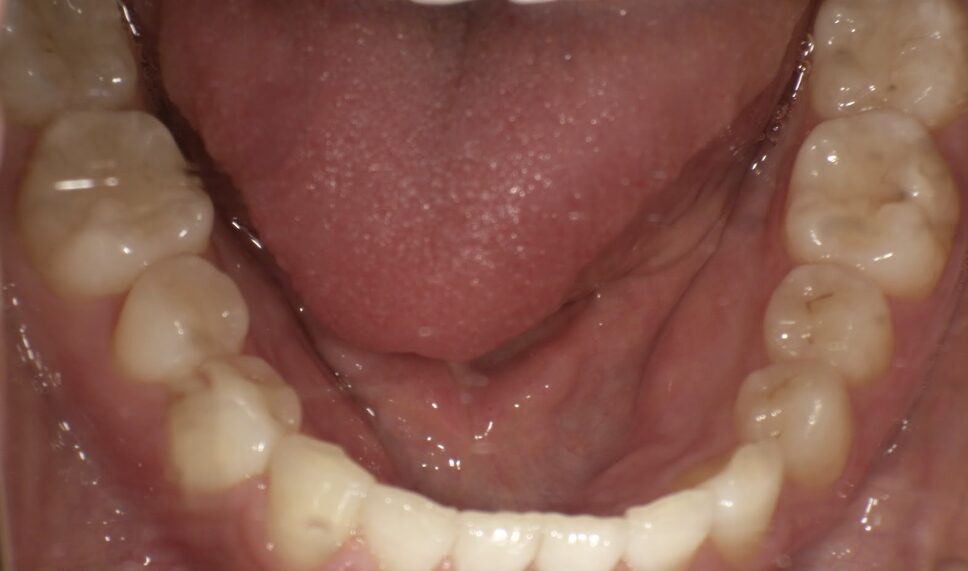

前歯のすき間が気になるを主訴に当院を受診され、前歯部空隙歯列(歯と歯の間に隙間が空いている状態)・過蓋咬合(上の歯が下の歯を深く覆いかぶさっている状態)・下顎前歯叢生(ガタガタ)を認めました。

IPRを使用してマウスピース型矯正装置(インビザライン)を使用し過蓋咬合及び叢生の改善を行いました。